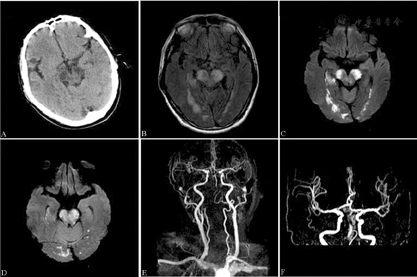

诊治过程:患者急性脑梗死诊断明确,入院后予氯吡格雷75 mg抗血小板聚集、阿托伐他汀20 mg调脂稳斑等治疗。患者入院第3天意识呈嗜睡状,不能言语,双侧眼球活动差,基本固定,右侧额纹减少,右眼睑闭合不全,咽反射检查及伸舌动作不能配合,吞咽困难,饮水呛咳,双上肢及右下肢未见自主活动,左下肢可遵嘱平移,双侧病理征阳性,NIHSS评分17分。患者入院第4天意识呈浅昏迷,四肢未见活动,NIHSS评分22分。头颅CT检查示颅内多发低密度片状影,考虑脑梗死灶(图2A)。头颅MRI示双侧小脑半球、脑干、枕叶、丘脑等多发新近梗死灶改变(图2B,图2C,图2D)。头颅MRA示:(1)双侧大脑后动脉纤细,显影不清;(2)右侧椎动脉V2~V4段以及左侧椎动脉V4段未见确切显影;(3)基底动脉纤细,显影浅淡(图2E,图2F)。患者病情仍进行性加重,持续昏迷状态,并伴发重症肺部感染。治疗6周余后出院继续康复治疗,出院时患者中度昏迷,四肢未见自主活动(四肢瘫),NIHSS评分22分,改良Rankin量表评分5分。出院数天后随访时患者死亡。

头颅CT扫描(A)示颅内多发低密度片状影,考虑脑梗死灶。头颅液体衰减反转恢复序列(B)和弥散加权成像(C、D)示双侧小脑半球、脑干、枕叶、丘脑等多发新近梗死灶改变。头颅磁共振血管造影(E、F)示:(1)双侧大脑后动脉纤细,显影不清;(2)右侧椎动脉V2~V4段以及左侧椎动脉V4段未见确切显影;(3)基底动脉纤细,显影浅淡

BCPI的确诊有赖于及时完整的头颅影像学检查。典型的BCPI在弥散加权成像(diffusion-weighted imaging, DWI)中双侧大脑脚呈高信号,犹如迪士尼动画片中米老鼠的2只耳朵,故Asakawa等[1]称之为"米老鼠耳征"(Mickey Mouse ears' sign)。也有中国学者将此病灶比同于中国汉字"八"[4]。本组2例BCPI患者的DWI图像也非常符合此征(图1C和图2C)。Asakawa等[1]对9例经头颅CT或MRI确诊的BCPI患者进行的统计显示,病变除双侧大脑脚外,多累及脑桥。陈文伙等[2]报道的14例BCPI患者也多累及脑桥、小脑、枕叶等后循环供血区域。Chen等[3]报道的11例BCPI患者多累及枕叶、小脑及丘脑等。本组病例1梗死灶相对局限,仅累及脑桥;病例2梗死灶相对广泛,累及脑桥、延髓、小脑及枕叶等多个区域。但是,这2例患者的影像学都提示椎基底动脉系统存在狭窄或闭塞。